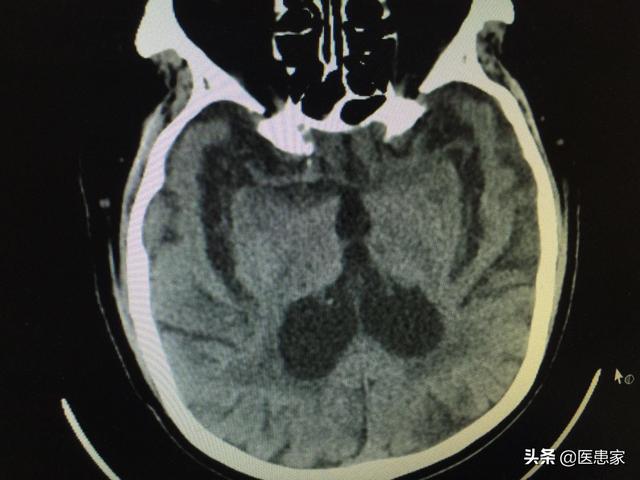

Tout d'abord, l'atrophie cérébrale ≠ "Alzheimer" (Parkinson). L'atrophie cérébrale n'est pas une maladie distincte, mais un symptôme objectif, c'est-à-dire le phénomène de rétrécissement du tissu cérébral, de diminution du nombre de cellules et d'élargissement des ventricules que l'on observe sur les examens d'imagerie tels que la tomodensitométrie, qui est une manifestation d'imagerie de nombreuses maladies.

L'atrophie cérébrale est un phénomène dans lequel le nombre et le volume des cellules cérébrales sont réduits et se manifestent morphologiquement par une atrophie due à des lésions organiques dans le tissu cérébral lui-même, causées par diverses raisons. La tomodensitométrie crânienne ou l'IRM peuvent montrer une réduction du volume du tissu cérébral et un élargissement des ventricules et de l'espace sous-arachnoïdien. La maladie survient généralement après 50 ans, peut durer des années, voire des décennies, et est plus fréquente chez les hommes que chez les femmes.

L'atrophie cérébrale n'est pas une démence et la gravité de la démence n'est pas proportionnelle à l'atrophie cérébrale. L'atrophie cérébrale est un phénomène dans lequel la tomodensitométrie cérébrale révèle une réduction de la taille du tissu cérébral, une diminution du nombre de cellules et un élargissement des ventricules.

L'atrophie cérébrale est un diagnostic d'imagerie. Lorsqu'un scanner ou une IRM du crâne révèle une diminution de la matière grise et un approfondissement des sillons, le médecin spécialiste de l'imagerie indiquera qu'il s'agit d'une "atrophie cérébrale". D'un point de vue pathologique, l'atrophie cérébrale se caractérise par une réduction de la taille du tissu cérébral, une diminution du nombre de cellules et un élargissement des ventricules et de l'espace sous-arachnoïdien. L'atrophie cérébrale n'est pas toujours pathologique, mais comprend généralement l'atrophie cérébrale physiologique et l'atrophie cérébrale pathologique.